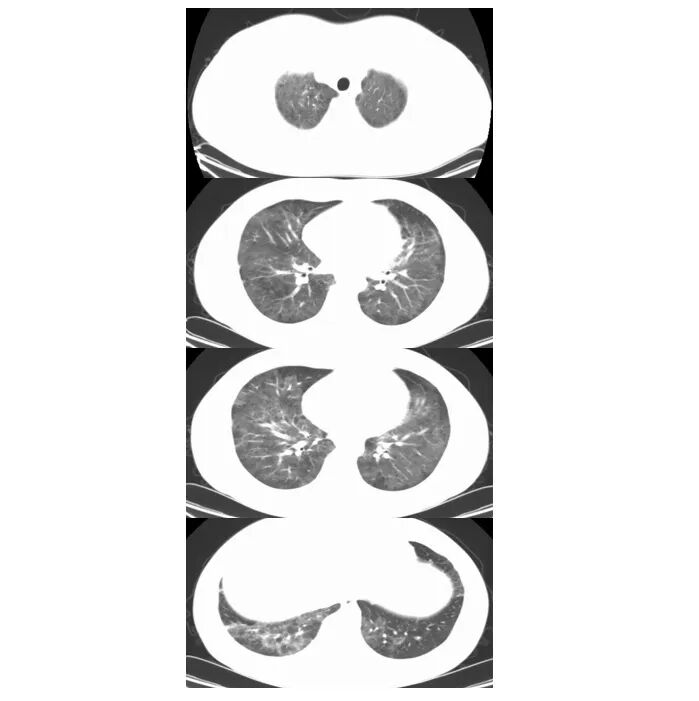

2024年12月11日胸部CT:双肺弥漫性病变

2. 亚急性起病,进行性气促,G试验升高(327pg/mL),影像学示“双肺弥漫性磨玻璃样病变”,符合肺孢子菌肺炎(pjp)的临床-影像特征。肺泡灌洗液tNGS:检出耶氏肺孢子菌(序列数40564),为pjp的确诊依据。